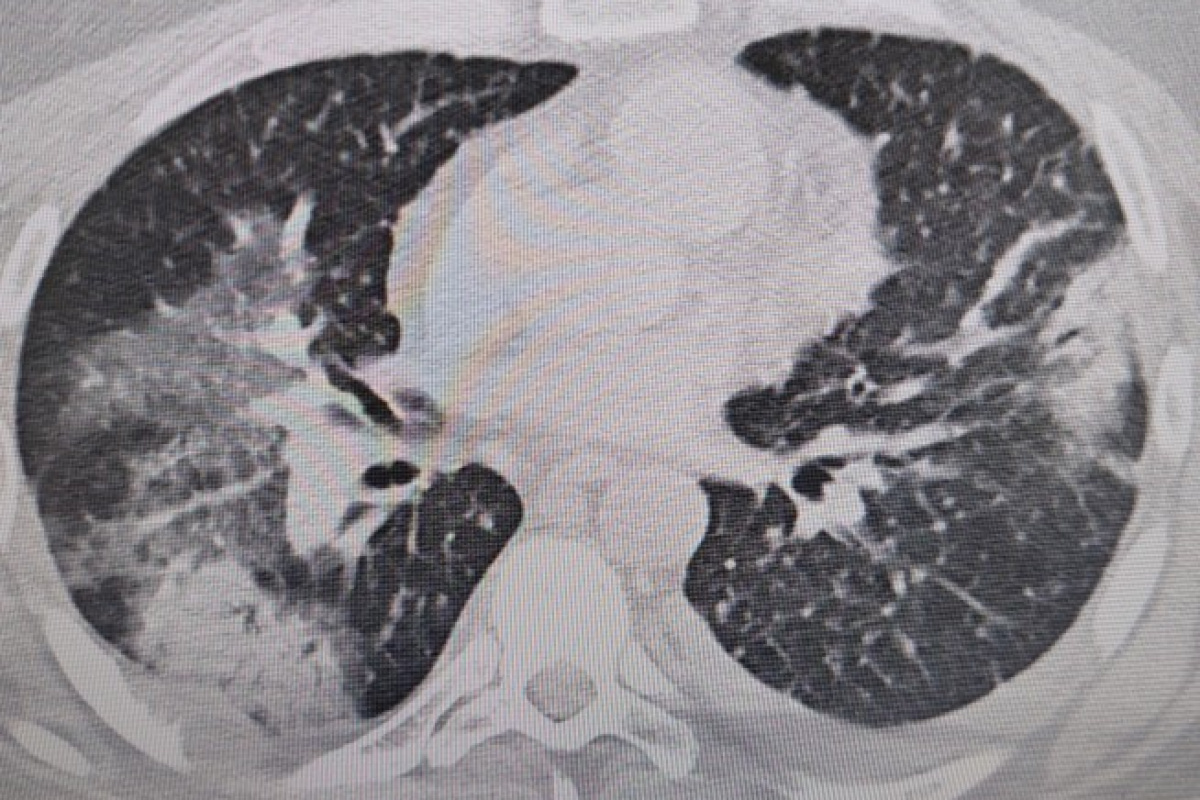

Prof. Dr. Şevket Özkaya, “Legionella” bakterisinin klima sularında üremesiyle insanların yaz zatürresine yakalandıklarını ve kış aylarına göre çok daha fazla vakayla karşılaştıkları bilgisini verdi. Klima zatürresinin özellikle kronik rahatsızlığı olanlarda ölümcül olabileceğini belirten Prof. Dr. Şevket Özkaya önemli uyarılarda bulundu. Özkaya, “Klimaların havalandırılmasıyla beraber insanlar ‘lejyoner’ bakterilerini akciğerlerine aldığında ‘klima pnömonisi’ ya da ‘yaz zatürresi’ dediğimiz hastalığa yakalanıyorlar. Bunun özellikle kronik astım, KOAH ve kanser hastalarında ölümcül sonuçlar doğurabileceğini biliyoruz” dedi.

Özellikle klimaların iyi temizlenmesi gerektiğini ifade eden Prof. Dr. Özkaya, “Klima zatürresinde grip gibi belirgin değil. Eklem ağrıları, ateş, halsizlik, ishal gibi hafif soğuk algınlığı belirtileriyle seyrettiği için de hemen anlaşılmayabilir. Özellikle kronik hastalığı olanlarda hayati sonuçlar doğurabilir. Ani ısı değişiklerine, örneğin sıcaktan soğuya ve klimalara maruz kalmakla oluşan belirtiler korona ile de karışabilir. Vatandaşlarımız, özellikle kapalı yerlerde kendilerine dikkat etsinler. Klima ayarlarını 22 derecenin altına düşürmesinler. Özellikle de bu ısı değişimlerine uzun süre maruz kalmamalarını öneriyorum” şeklinde konuştu.